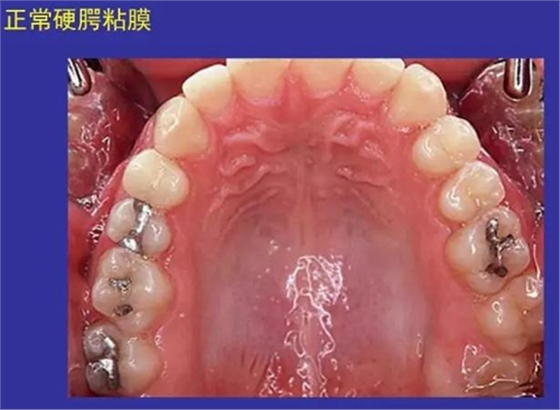

一、正常口腔黏膜圖

正常口腔黏膜及常見病損圖